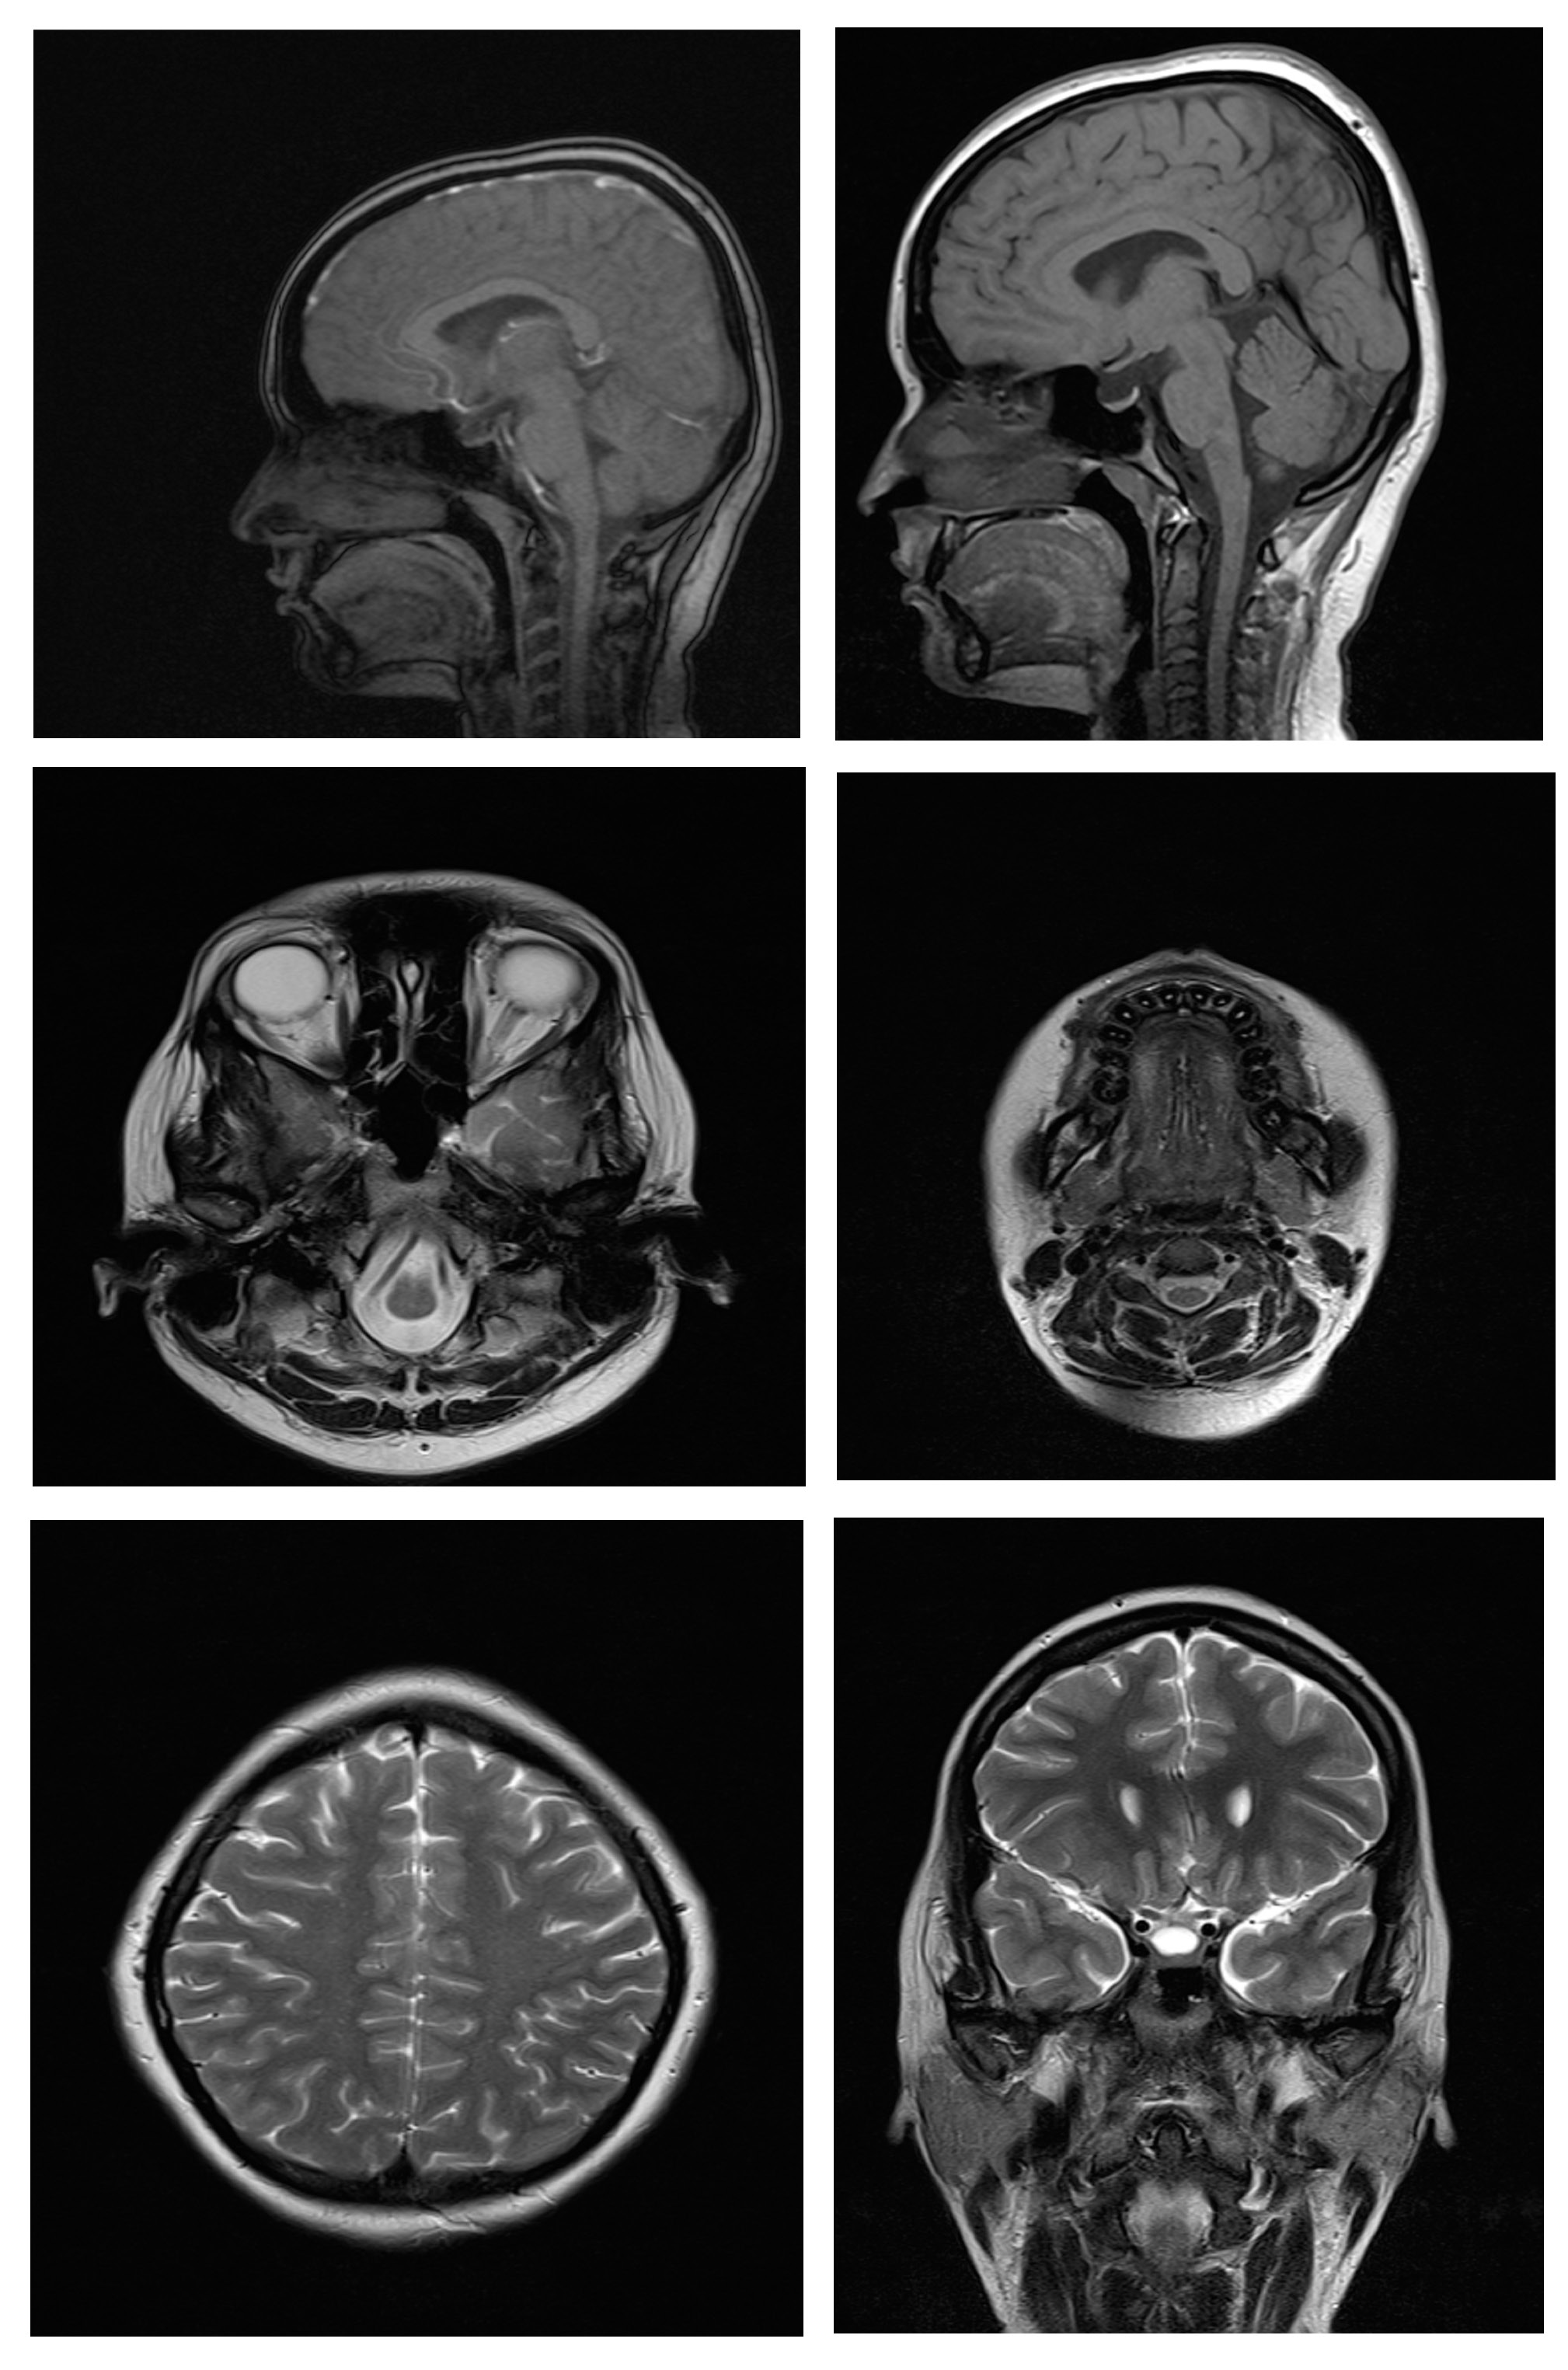

Magnetic resonance imaging scans were taken for all 38 subjects to study diagnostic image quality. Since the orthodontic appliances were securely bonded with orthodontic composite, there were no special precautions taken regarding the possible dislodgement and heating of the appliances, as previous studies had found changes in the temperature of the appliances to be clinically insignificant (within 1°C).16 The MRI scans for all types of bracket and retainer materials are shown in Figure 1, Figure 2, Figure 3, Figure 4, Figure 5, Figure 6, Figure 7, Figure 8, Figure 9, Figure 10. Non-diagnostic or unclear ROI are marked with arrows. None of the patients reported any discomfort or pain during MRI examination. The MRI scans were analyzed by a panel of 6 qualified and licensed radiologists, who assessed their diagnostic quality. The scans were compared with controls that included images from the archives of the Department of Radio-Diagnosis of Kamineni Institute of Medical Sciences. The radiologists ranked the images according to the distortion observed in the abovementioned ROI, using the modified receiver operating characteristic (ROC) analysis of distortion scoring system (Table 2), as described by Elison et al.17 In this method of distortion classification, a score of 3 represents the cut-off point for clinical usability. Images with a score of 3 have moderate distortion or artifacts, but they can still be used for diagnosis.

In recent years, many new fixed retainers have entered the market. Some of them include titanium retainers, fiber-reinforced composite retainers and braided titanium retainers. Retention is an important aspect in orthodontics. Many patients need to have fixed retainers for an extended period of time and may require MRI for various reasons during that time; hence, 3 types of fixed retainers and 2 combinations of them were evaluated for their influence on the diagnostic image quality of MRI scans. To date, there are no comprehensive MRI studies on these fixed retainers and combinations of these retainers in both arches.

Stainless steel retainers in both the maxillary and mandibular arch had a mean distortion score of 2.00. The mean distortion scores at the anatomic sites were 2.16 for TMJ, and 2.00 for the tongue, the maxilla, the mandible, and the maxillary sinus, with only the posterior cerebral fossa having a score of 1.00. This means that there was minimal or no distortion for all ROI. Hence, the MR images with stainless steel retainers in the maxillary and mandibular arches were considered diagnostic.

Titanium retainers in the mandibular arch alone had a mean distortion score of 2.00. The mean distortion scores at the anatomic sites were 2.16 for TMJ, 2.00 for the tongue, the maxilla, the mandible, and the maxillary sinus, and 1.00 for the posterior cerebral fossa, which indicates that there was minimal or no distortion for all ROI. Hence, the MR images with titanium retainers in the mandibular arch alone were considered diagnostic. The results of this study are similar to the findings reported in studies by Shalish et al.,28 Beau et al.24 and Zhylich et al.25

Fiber-reinforced composite retainers in the mandibular arch alone had a mean distortion score of 1.00 and mean distortion scores of 1.00 at all 6 anatomic sites, which means there was no distortion for any ROI. Hence, the MR images with fiber-reinforced composite retainers in the mandibular arch only were considered diagnostic. There are no studies reporting on this type of retainers.